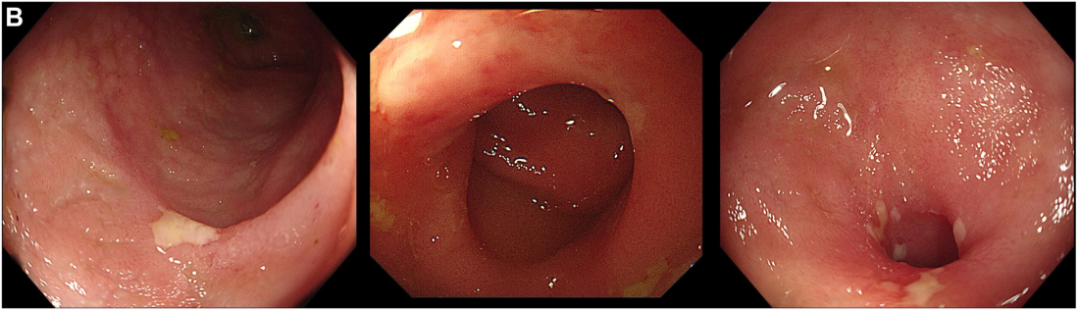

病史摘要:患者为 57 岁男性,因黄疸、间歇性发热及体重减轻 7 个月就诊。既往有结核性胸膜炎、高尿酸血症、肺腺癌肺叶切除术、高脂血症、冠心病等病史。10 个月前有一过性多饮多尿,3 个月前眼周及口周出现黄色皮疹并蔓延。 诊疗过程:血液检查有轻度贫血、胆汁酶及 IgG4 轻度升高。MRCP 显示肝内胆管扩张等,内镜检查未发现恶性病变。初步疑诊 IgG4 相关性硬化性胆

腹泻3年+小肠溃疡+黏膜萎缩,大剂量泼尼松治疗无效,这种极易漏诊的罕见病如何破局?